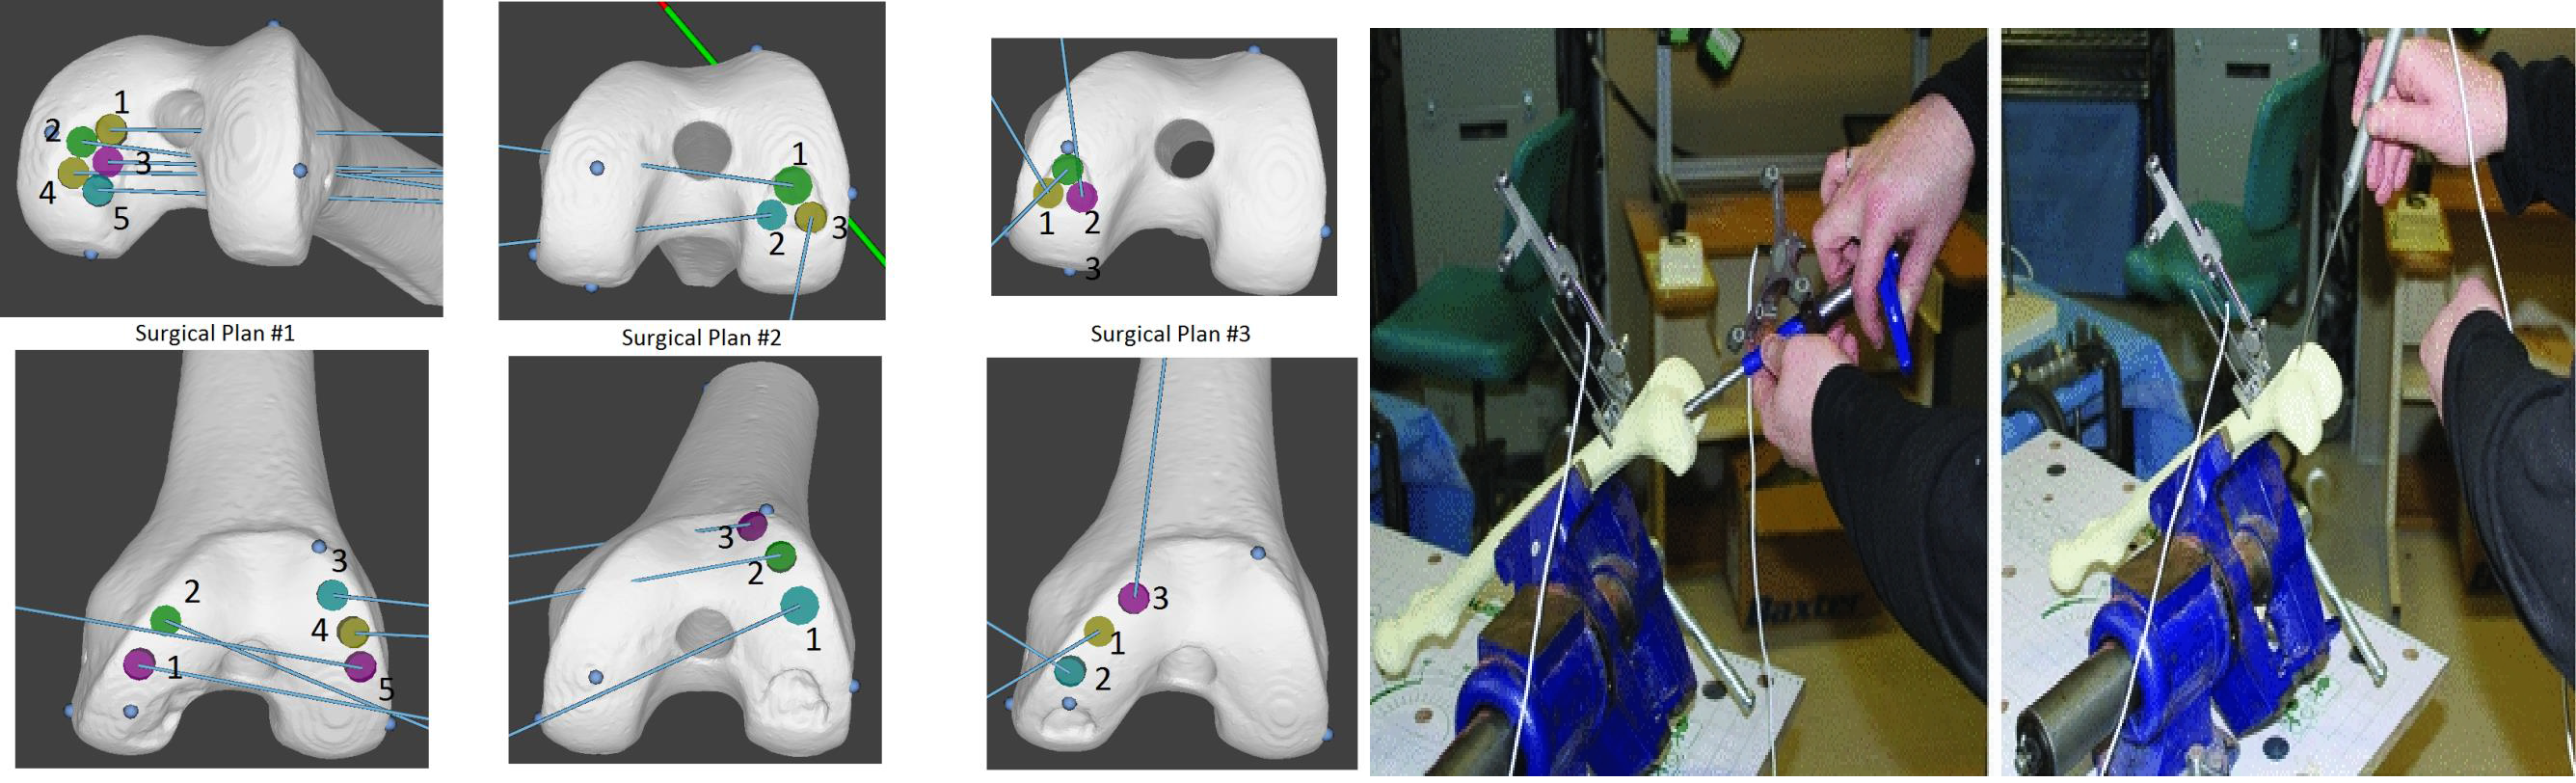

The initial step is acquiring preoperative diagnostic CT (or MR) and segmenting the joint. Segmentation can be achieved semi-automatically using thresholding, edge detection, and region growing methods, but the region of interest (the lesion) is typically manually segmented (or edited). The patient’s ideal curvature is recreated by consultation with the surgeon using a manual planner (Dr. Kunz and others) or planning software (originally designed by Dr. Jiro Inoue, PhD). Using the reconstructed joint, surgical sites are planned.

Method 1 - Custom Template Guides

One approach uses thermo-plastic templates. Using reconstructed patient knee models, surgical sites are planned and used to design thermoplastic templates that are 3D-printed. These templates fit the patient’s joint and guide the surgical instrument from harvest to recipient site (accounting for 6 degrees of freedom).

Method 2 - Optical Electronic Guidance

The other method involves attaching optical LED markers and tracking instruments using a stereoscopic camera (analogous to tracking used in motion-gaming systems, but with significantly greater reliability and accuracy). The surgical plan is overlaid on the patient’s model. The system is calibrated using 3D-printed and machined calibration blocks. Then, using an ICP-variant, the patient’s joint is registered with the computational model. The navigation system tracks instruments relative to the joint surface, providing visual feedback (6 DOF) to the surgeon.

This process is significantly more accurate than the conventional procedure and only marginally less accurate than the template method. It is more time-consuming due to calibration/registration steps, but has the advantage of being usable in less-invasive arthroscopic variants.